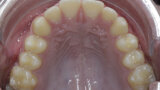

New Age orthodontics and orthopaedics with temporary anchorage devices